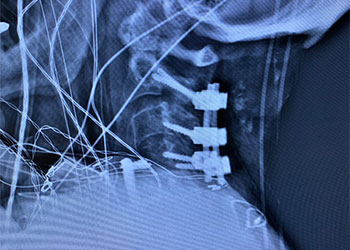

Back:

Revision Surgery Treats Intractable Neck Pain & Cervical Deformity

Author: Benjamin R. Cohen M.D., F.A.A.N.S., F.A.C.S., Read More!